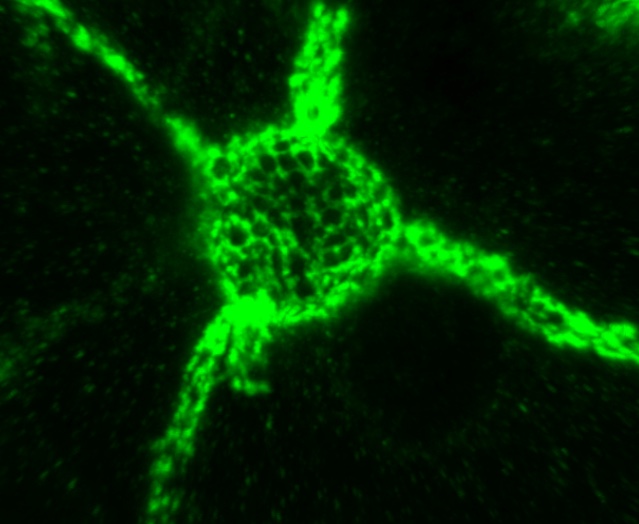

L'immagine mostra una rete perineuronale (verde) che circonda un neurone. (Fonte: Kristian K. Lensjø)

In precedenza, i ricercatori si erano concentrati principalmente sulle molecole all'interno delle cellule nervose. Il team di investigatori, guidato dai Dott. Marianne Fyhn e Torkel Hafting, hanno studiato le reti perineuronali che ricoprono strettamente l'esterno dei neuroni. Le reti sono costituite da proteine rivestite di zucchero, e formano una struttura rigida che contiene fori in cui vengono mantenute le connessioni con altri neuroni.